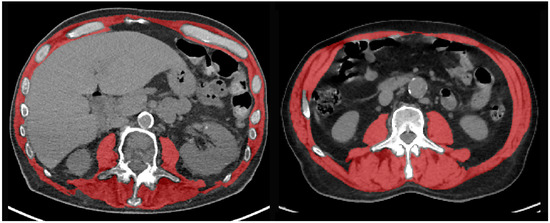

2.5. Sarcopenia Measures

- Ibtehaz, N.; Rahman, M.S. MultiResUNet: Rethinking the U-Net architecture for multimodal biomedical image segmentation. Neural Netw. 2020, 121, 74–87. [Google Scholar] [CrossRef] [PubMed]

- Koitka, S.; Kroll, L.; Malamutmann, E.; Oezcelik, A.; Nensa, F. Fully automated body composition analysis in routine CT imaging using 3D semantic segmentation convolutional neural networks. Eur. Radiol. 2021, 31, 1795–1804. [Google Scholar] [CrossRef]

- Graffy, P.M.; Liu, J.; Pickhardt, P.J.; Burns, J.E.; Yao, J.; Summers, R.M. Deep learning-based muscle segmentation and quantification at abdominal CT: Application to a longitudinal adult screening cohort for sarcopenia assessment. BJR 2019, 92, 20190327. [Google Scholar] [CrossRef]

- Burns, J.E.; Yao, J.; Chalhoub, D.; Chen, J.J.; Summers, R.M. A Machine Learning Algorithm to Estimate Sarcopenia on Abdominal CT. Acad. Radiol. 2020, 27, 311–320. [Google Scholar] [CrossRef]

- Mourtzakis, M.; Prado, C.M.M.; Lieffers, J.R.; Reiman, T.; McCargar, L.J.; Baracos, V.E. A practical and precise approach to quantification of body composition in cancer patients using computed tomography images acquired during routine care. Appl. Physiol. Nutr. Metab. 2008, 33, 997–1006. [Google Scholar] [CrossRef] [PubMed]